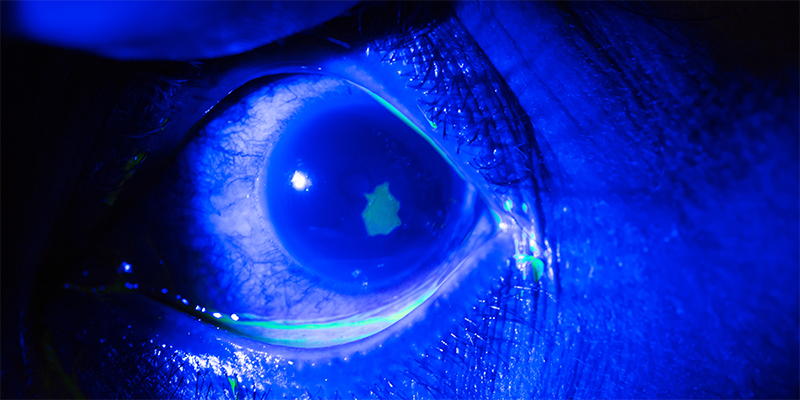

De NHG-Standaard Rood oog en oogtrauma adviseert om eenmalig een antibiotische oogzalf aan te brengen bij een traumatische cornea-erosie. Deze aanbeveling is echter met name gebaseerd op expert-opinion. Een recente cochranereview laat zien dat er tot nog toe geen bewijs is dat profylactisch antibiotica een ooginfectie voorkomt of het genezingsproces versnelt.

De auteurs van de cochranereview vonden geen artikelen die antibiotica vergeleken met placebo of geen behandeling. Ze includeerden 2 RCT’s. In een Deense trial werd chlooramfenicol met fusidinezuur vergeleken (n = 153). In een Indiase trial chlooramfenicol/clotrimazol met chlooramfenicol/placebo (n = 374) bij patiënten met een cornea-erosie.

De Deense trial liet een vergelijkbare genezing zien van de cornea-erosie zonder tekenen van infectie na één dag (44,3% vs. 46,6%). In beide groepen werden bij één derde van de deelnemers milde bijwerkingen beschreven als jeuk en irritatie van het oog.

De Indiase trial liet ook een vergelijkbare genezing zonder infectie in beide groepen zien (100% vs. 99%) na 3 dagen behandeling. In deze studie werd slechts bij 2% van de deelnemers milde irritatie gemeld.